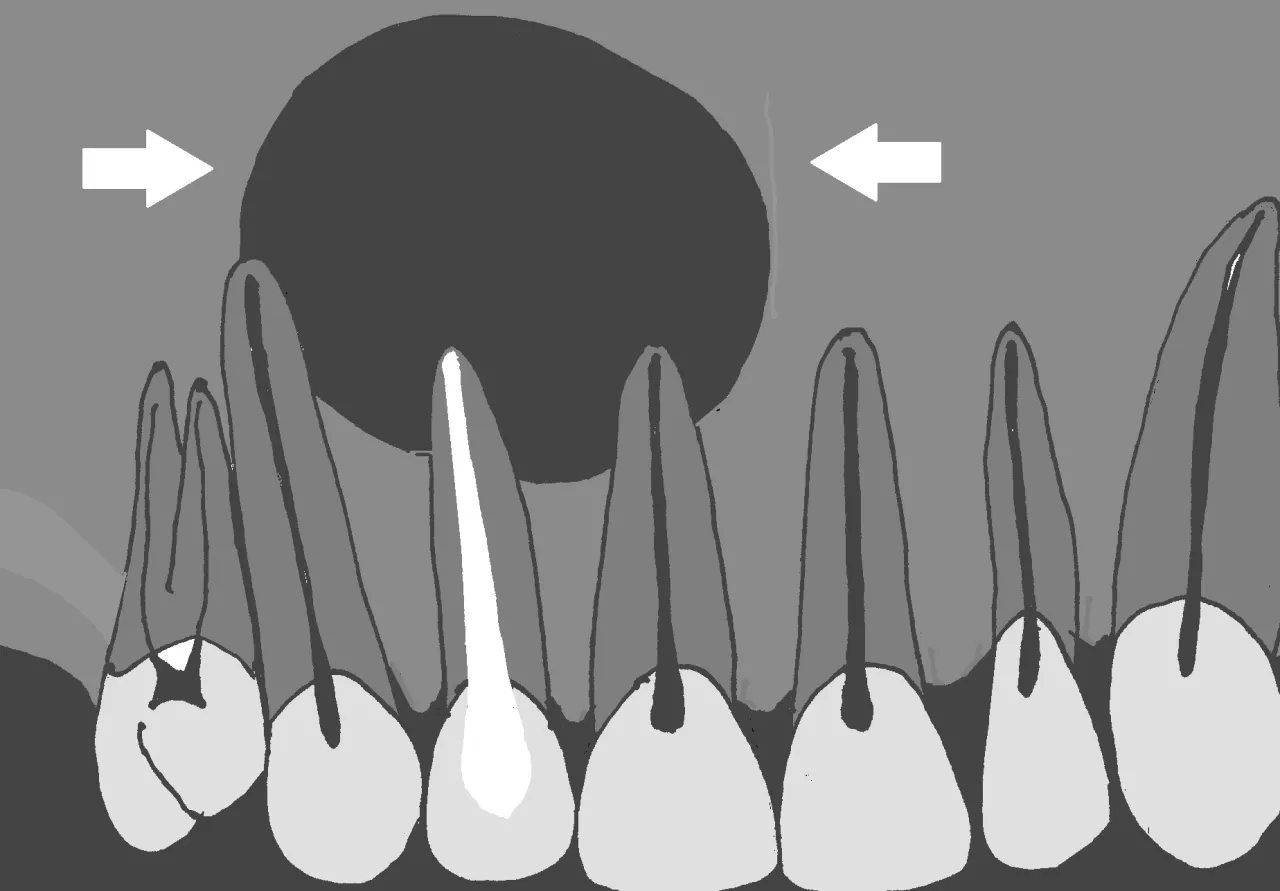

Podstawą diagnozy torbieli jest wizyta u stomatologa, który przeprowadzi dokładne badanie jamy ustnej. Jednak sam ogląd i palpacja często nie wystarczą, aby ocenić charakter i rozmiar zmiany, zwłaszcza jeśli znajduje się ona przy korzeniu zęba. Dlatego kluczową rolę odgrywa diagnostyka obrazowa. Podstawowym badaniem jest zdjęcie rentgenowskie pantomograficzne (obejmujące całe uzębienie) lub punktowe (skupione na konkretnym zębie). Pozwala ono uwidocznić zmiany kostne wokół wierzchołka korzenia, które są typowe dla torbieli.

Nieleczona torbiel, mimo że często rozwija się bezboleśnie, stanowi realne zagrożenie dla zdrowia. Jej powolny wzrost prowadzi do stopniowego niszczenia kości szczęki lub żuchwy, w której jest zlokalizowana. Może to osłabić zęby znajdujące się w pobliżu, prowadzić do ich przemieszczenia, a w skrajnych przypadkach nawet do utraty zębów. Co gorsza, postępujące niszczenie kości może zwiększać ryzyko tzw. złamań patologicznych, czyli złamania kości pod wpływem niewielkiego urazu.